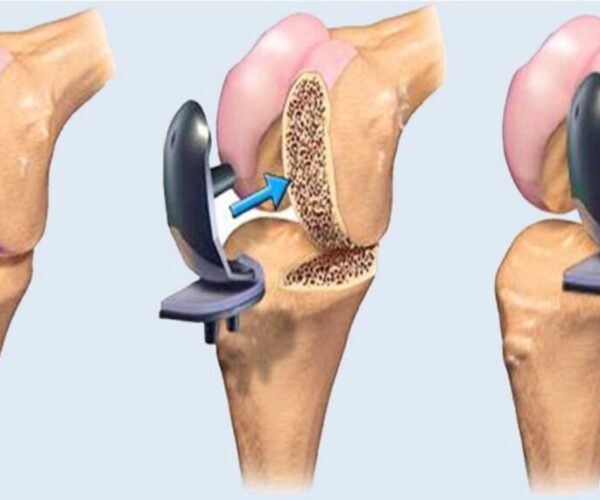

Best Orthopaedic Hospital for Knee Replacement in Ahmedabad Best Orthopaedic Hospital for Knee Replacement in Ahmedabad – Dr. Urang Patel at HCC Hospital If.